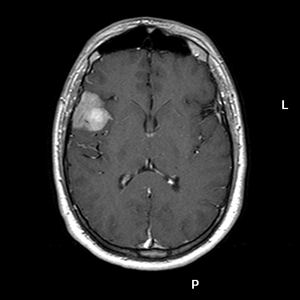

EXPLORACIONES RADIOLÓGICAS:

TAC: Proceso expansivo frontoparietal derecho.

RM: Tumor localizado en valle silviano ¿intra- extraaxial? de 34 x 25 mm.. La lesión se rodea de mínimo edema y no presenta efecto masa significativo. (Figs. 1-2)

Fig. 1. Corte axial T2 mostrando lesión hiperintensa en valle silviano. ¿intra-extraaxial? Fig. 2. Corte axial T1 con contraste, captación intensa.